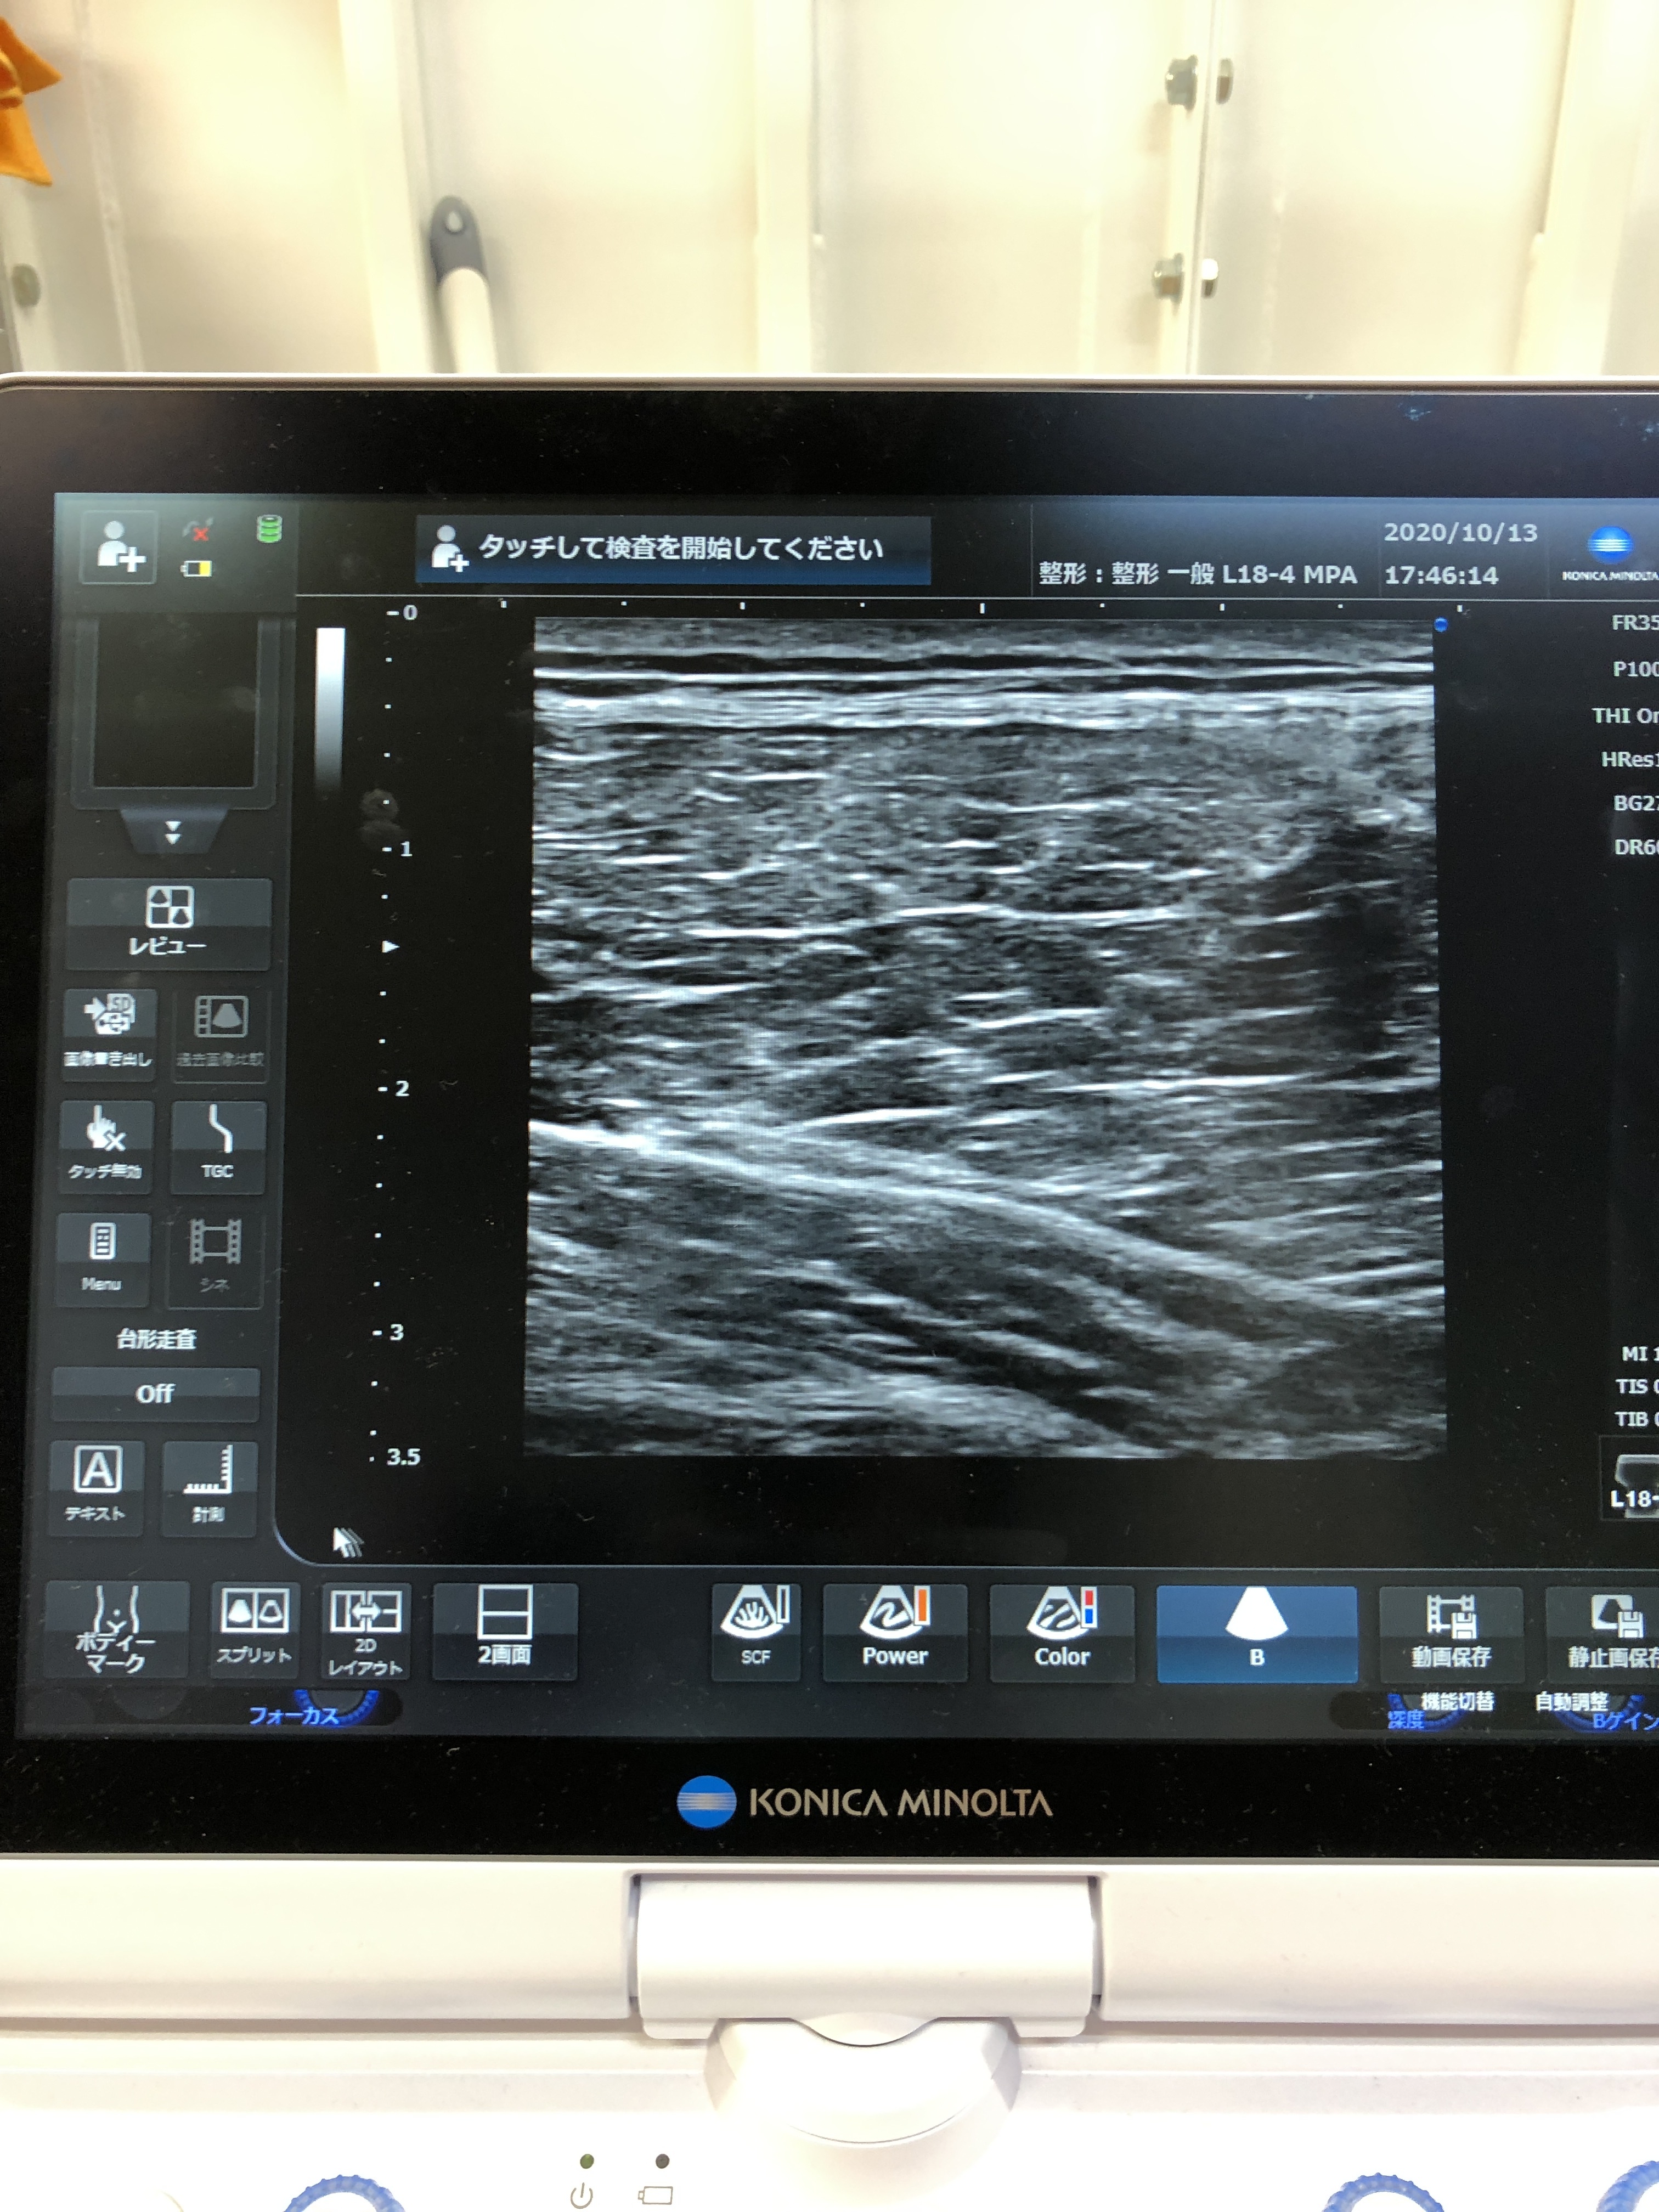

超音波エコーで筋肉をみてみましょう!

太腿の筋肉の大腿四頭筋を見ていきましょう!

今回はその中でも、大腿直筋という1番浅い筋肉をみていきます!

↓↓↓↓↓↓↓↓↓↓↓↓↓↓↓↓↓↓↓

筋肉はこのように画像として写ります!

焼肉のカルビなどの中の繊維を思い出してください!

きれいに均等な向きでそろっているのが普通です!

痛めると、しこりみたいになったり、腫れが写ったり、固さが画像として出たりします!